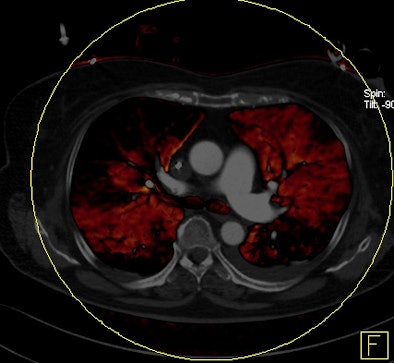

Dual-energy CT enables the selective display of iodine distribution within the pulmonary parenchyma following contrast-enhanced pulmonary CT angiography, which in turn permits the calculation of perfusion defect (PD) size in patients with suspected PE.

Depending on the shape and pattern of the defects at dual-energy CT, perfusion defects due to PE can generally be distinguished from, for example, patchy defects signaling other pathologies of the lung parenchyma, Bauer said.

The researchers measured perfusion defect size in the lung parenchyma caused by PE on dual-energy iodine distribution maps, and expressed it in two ways: as absolute quantification (VolPD in mL) and relative to the total lung volume (RelPD in %).

| Patient with bilateral segmental and subsegmental PE and large perfusion defects on dual-energy iodine distribution maps. All images courtesy of Dr. Ralf Bauer. |